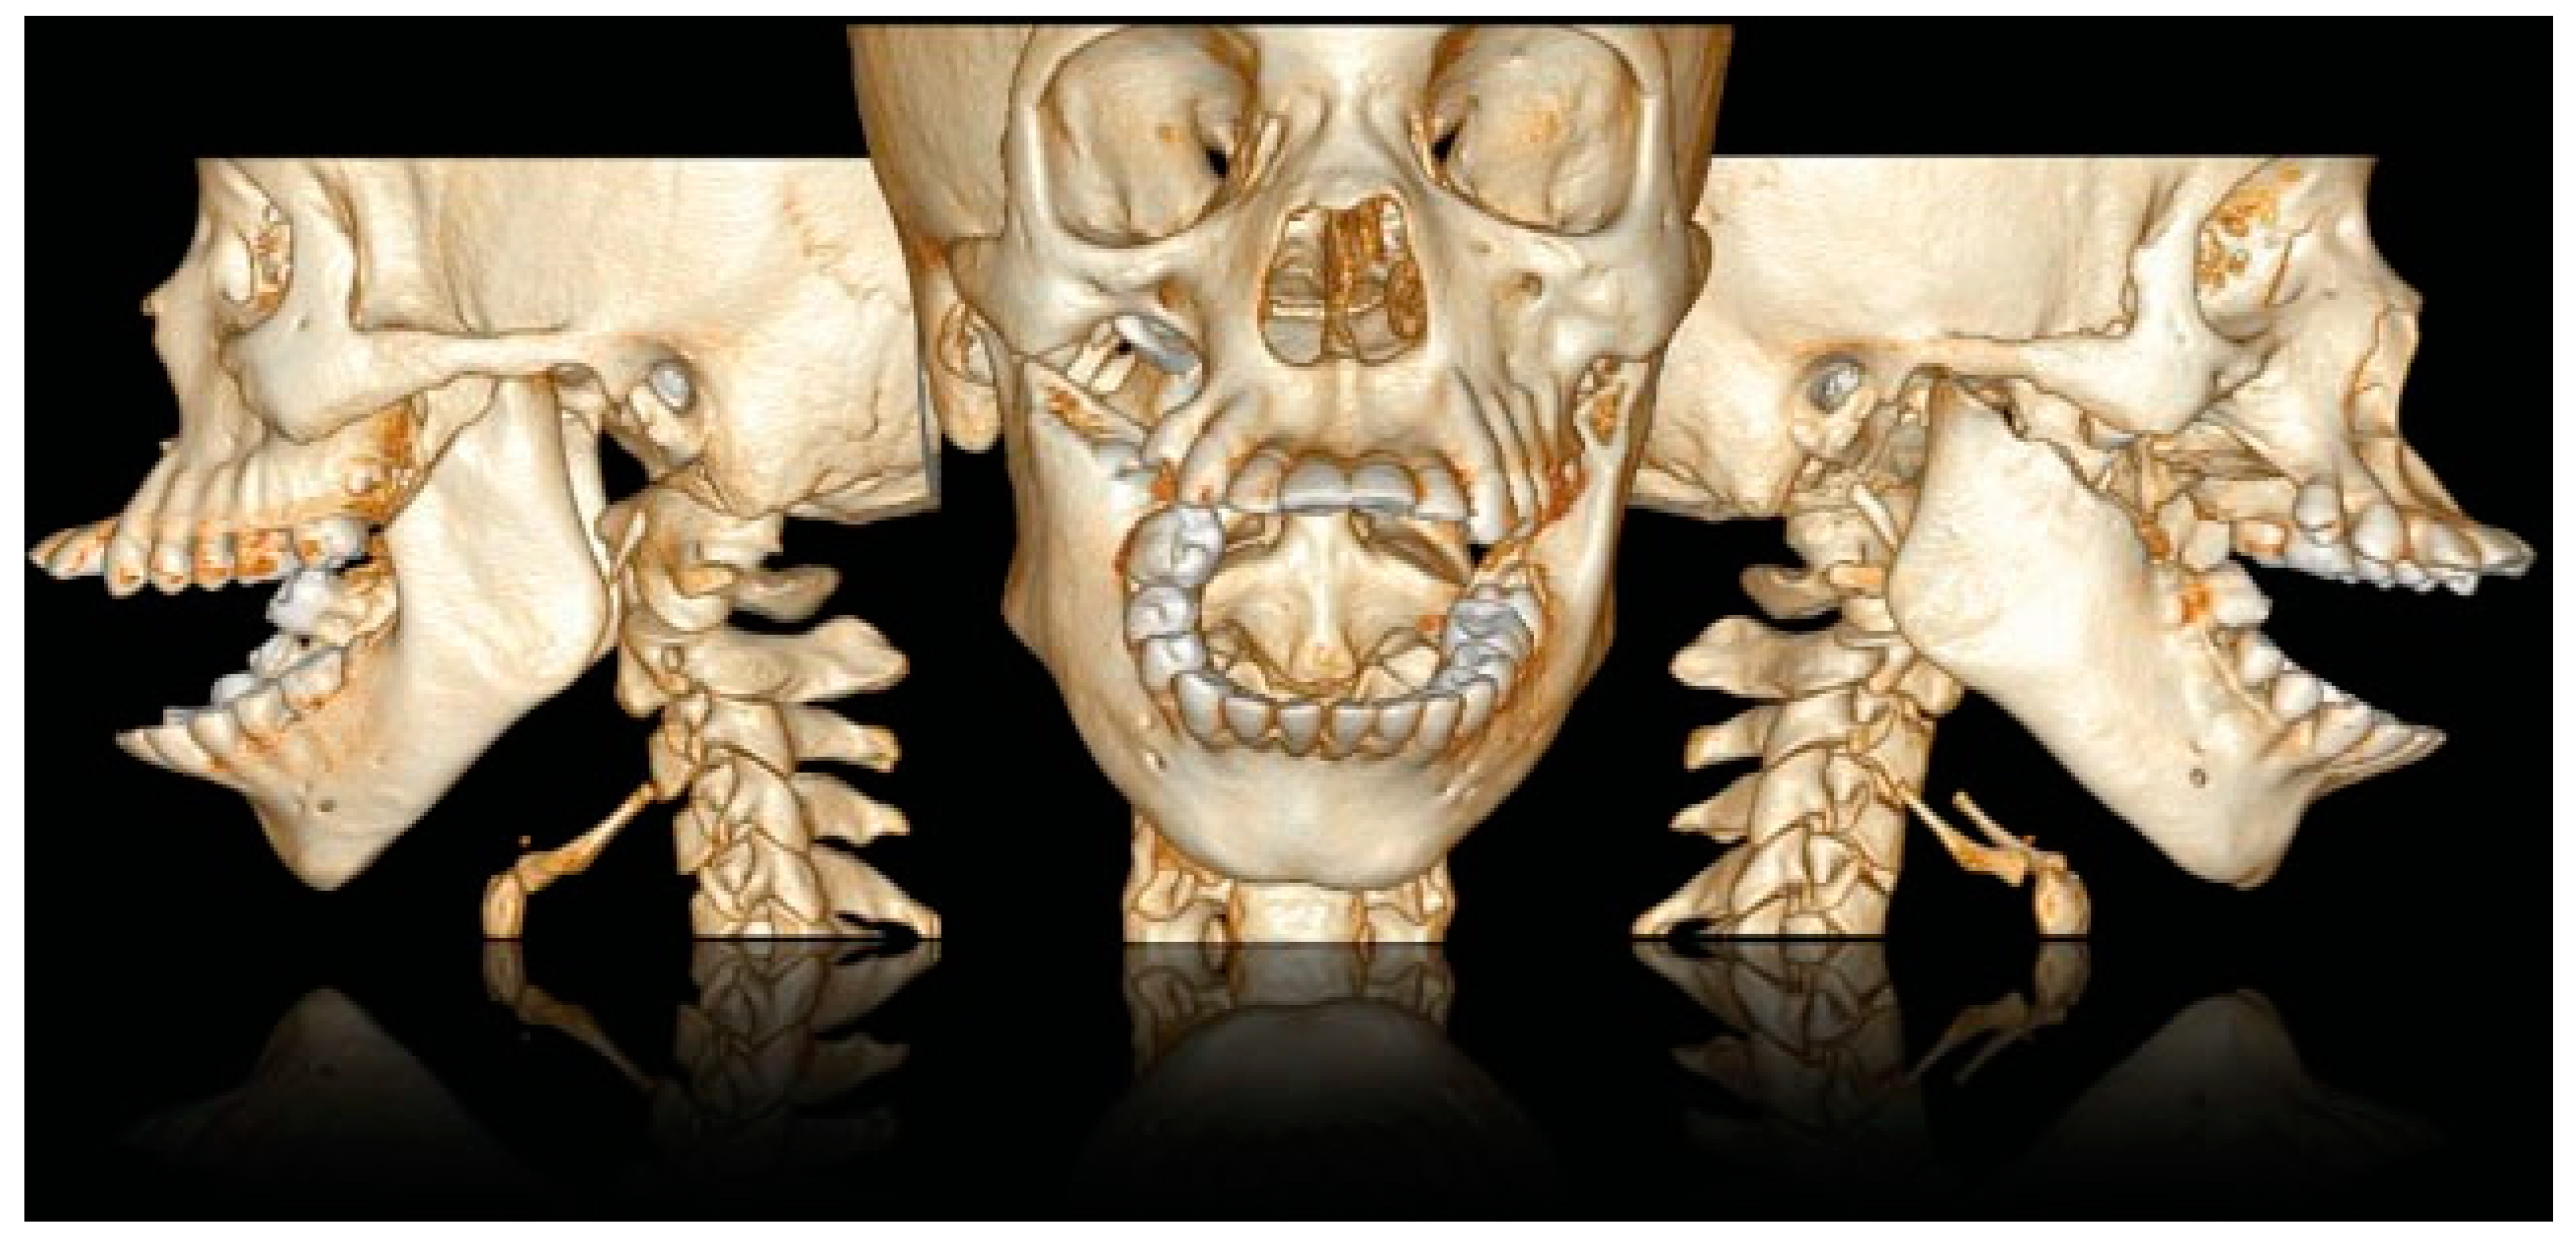

Figure 5. CT scan with 3D reconstruction: upper and lower jaw dental collapse with labioversion, dental agenesis, and right hemifacial microsomia.

A CT scan of the head with 3D reconstruction (Figure 1, Figure 2, Figure 3, Figure 4 and Figure 5) confirmed a maxillomandibular fusion associated with a cleft palate, agenesis of the right turbinate, and right hemifacial microsomia (Laster type 2b syngnathia). Both temporomandibular joints (TMJs) were normal and showed no bony ankylosis (fibrous ankylosis could not be excluded with the given data).

This patient can be considered as a complex zygomaticomandibular syngnathia or type 2b, because of the bony fusion of the mandible to the zygomatic complex associated with a palatal cleft, hemifacial microsomia, agenesis of the right turbinate, and dental agenesis (elements 15, 16, 17, and 18). The patient has the highest age at diagnosis described in the literature.